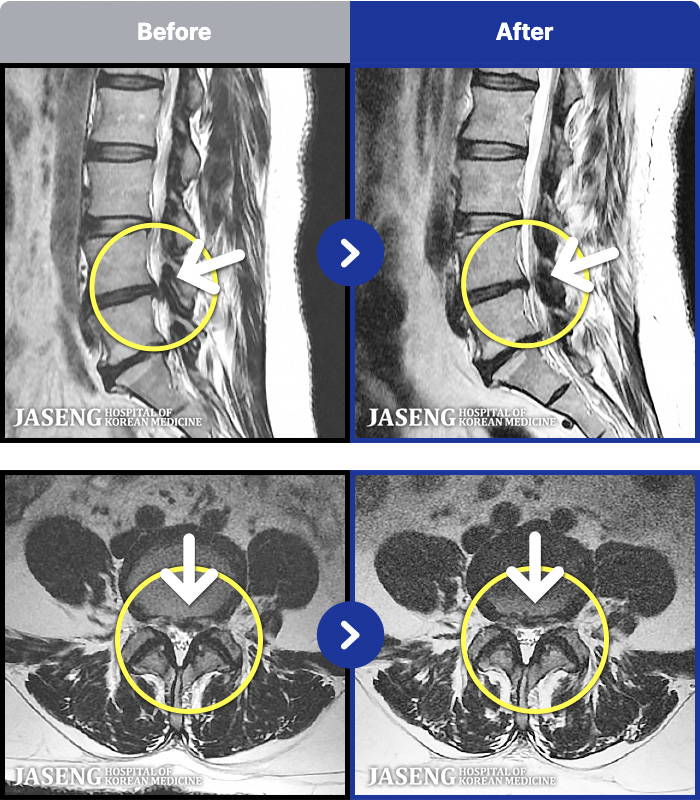

- MRI ġ

MRI ġ

1,301 MRI ũ ʸ Ȯϼ.